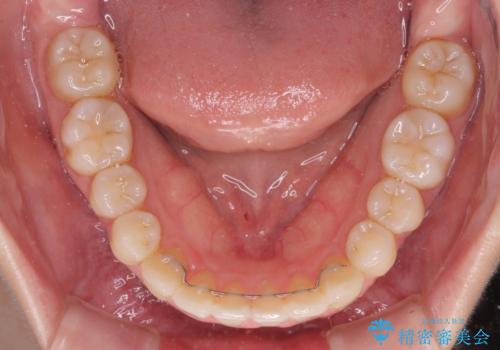

- 上下前歯のデコボコを気にして来院された患者様です。

インビザラインによる上下歯列の側方拡大と後方移動、IPR(歯と歯の間を削る)にるスペースの獲得により歯列を整えることとしました。

1日22時間の装着時間をしっかり守ってくださったので、予定していた1年よりも早く治療を終えることができました。

インビザライン矯正特有の奥歯がしっかりと咬合しない感覚も改善され、大変満足していただきました。